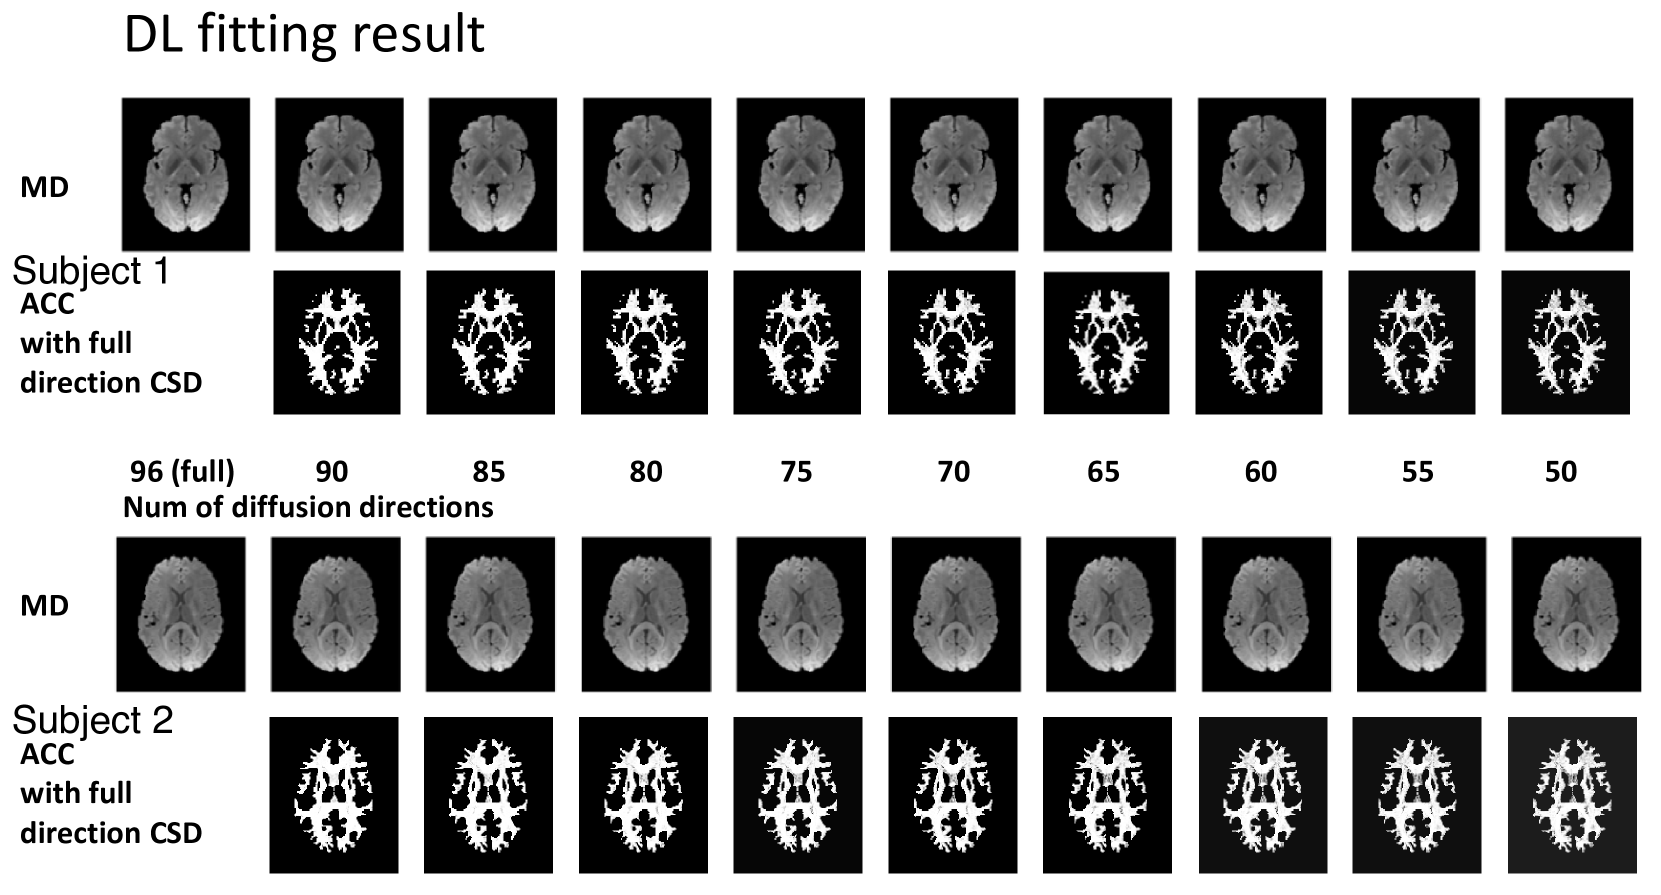

In the ablation study (Table 3), we evaluate the intra-subject augmentation by comparing the intra-subject consistency on all white matter voxels with different number of diffusion directions. The deep learning model which has the best performance on the validation set is chosen for comparison. In Fig. 3, the right side shows a qualitative result of the visualization of the estimated SH coefficients and the left side shows the comparison with full-direction CSD. By performing CSD, the test subjects with a mean of 72 diffusion directions can only maintain a mean ACC of 0.848 as compared with their same acquisition with 96 directions. By adding the intra-subject augmentation during the training process, both voxel-wise and patch-wise models have significant improvement, which shows that deep learning reveals untapped information during the ODF estimation. Fig. 4 shows the result of 1) estimation on a signal with fewer diffusion directions using a patch-wise DL model with scan/rescan data and intra-subject augmentation participated during training and 2) CSD reconstruction result.

Fig. 6 and Fig. 7 provide an additional qualitative visualization of the robust deep learning fitting during diffusion direction dropout. In Fig. 6 we plot the mean diffusivity and the ACC spatial map where MD indicates the fitting of the 0thsuperscript0𝑡0^{th}0 start_POSTSUPERSCRIPT italic_t italic_h end_POSTSUPERSCRIPT order coefficients (No.1 in 45) and the ACC focus on the rest of the SH coefficients (No.2-45 in 45). In Fig. 7, we focus on two unique voxels belonging to the single fiber population and crossing fiber population respectively, the result shows that CSD reconstruction has an obvious shapeshift in the low-resolution scheme while deep learning with the data augmentation strategies remains higher consistency, especially in the visualization of the crossing-fiber voxel.

Figure 6: Qualitative visualization of the predicted coefficients in fewer diffusion directions scenario. The mean diffusivity map(MD, 0thsuperscript0𝑡0^{th}0 start_POSTSUPERSCRIPT italic_t italic_h end_POSTSUPERSCRIPT order of the SH coefficient) and ACC agreement spatial map (even orders of the SH coefficient without 0thsuperscript0𝑡0^{th}0 start_POSTSUPERSCRIPT italic_t italic_h end_POSTSUPERSCRIPT order, compared with the silver standard–full direction CSD) of deep learning results of the two MASiVar test subjects. The dropout was performed from 96 to the subset of 45 directions while the visualization was shown at intervals of every 5 diffusion directions.